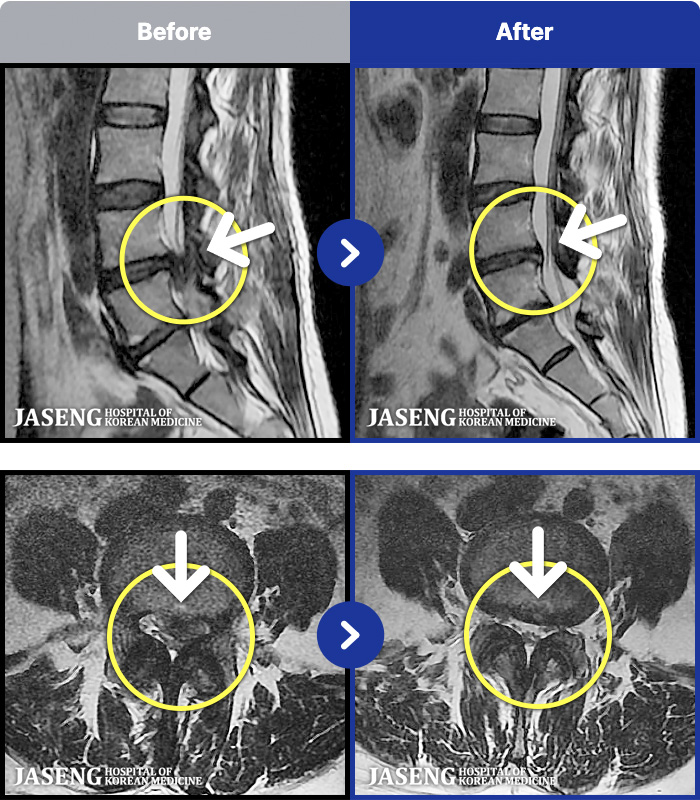

MRI ġ

1,299 MRI ũ ʸ Ȯϼ.